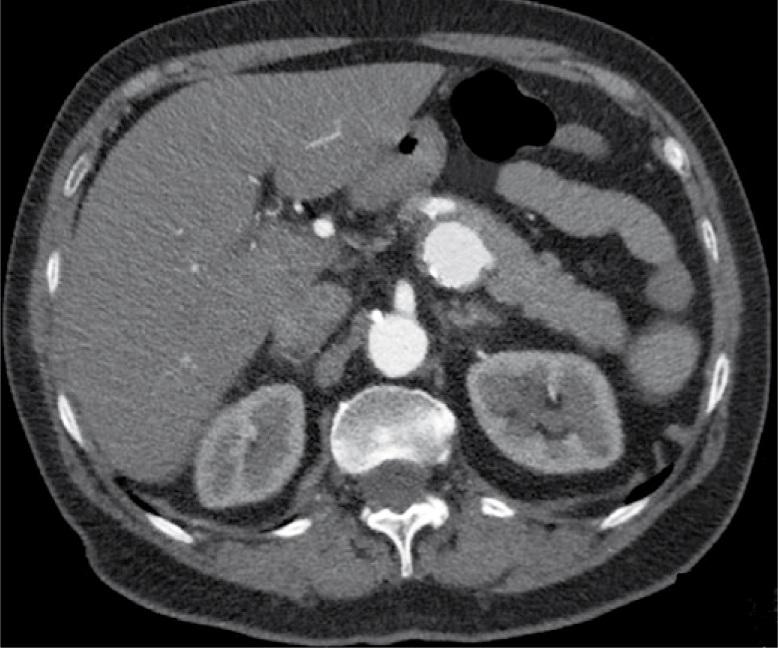

Een 73-jarige vrouw met hypertensie presenteerde zich op de SEH met hevige buikpijn die continu sinds 10 h aanwezig was. Ook was zij misselijk en had zij gebraakt. Bij lichamelijk onderzoek zagen wij een zieke vrouw met pijn, zonder koorts. Patiënte was hemodynamisch stabiel. Peri-umbilicaal gaf zij percussie- en loslaatpijn aan. Laboratoriumonderzoek toonde geen afwijkingen.

Wat is uw diagnose?

Antwoord